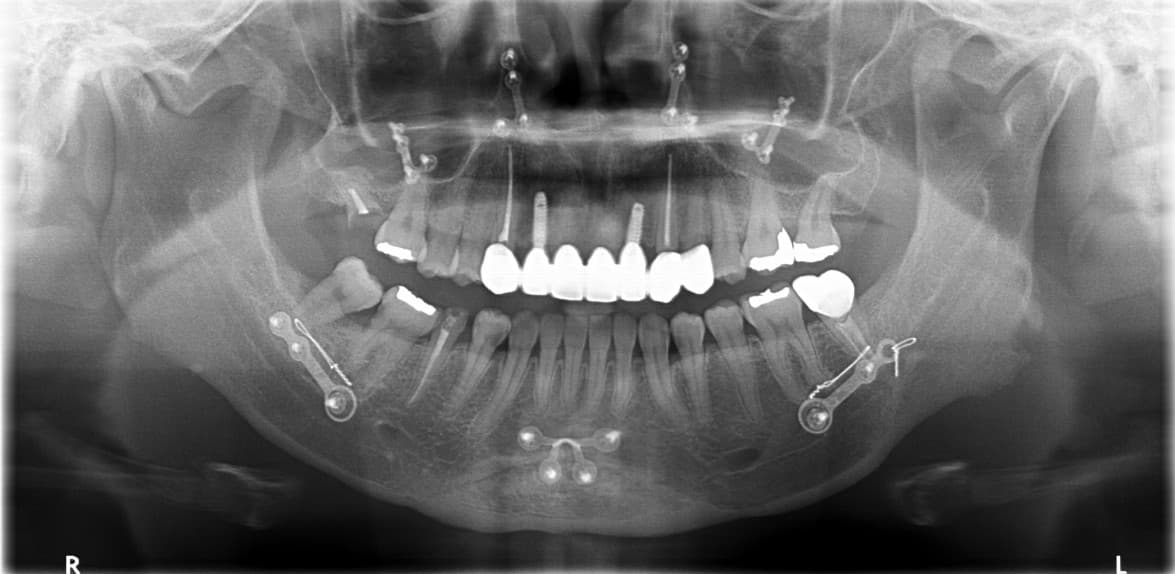

Complex Cases

Full Mouth Reconstruction

Before & After

Cases of completely damaged oral health

restored to normal daily life

Comprehensive Treatment by Prosthodontist

Front Teeth Implant · Ms. K●● · Female, 50s

Front Teeth Implant · Mr. L●● · Male, 60s